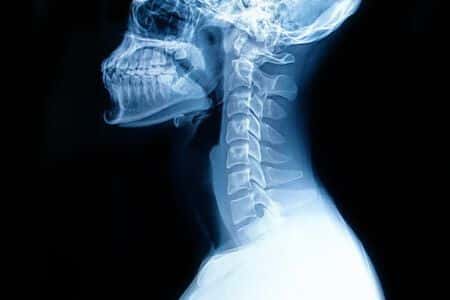

This case takes place in Missouri and involves a female patient who underwent fusion surgery on her upper spine. The patient was discharged but later returned to the ER with signs of sepsis from the surgical site, and was consequently was admitted to the ICU. A scan of the upper spine did not reveal evidence of an infection or any other damage to the spine. However, it did not rule out damage at another level of the spine, and did not explain the patient’s symptoms. Some time after initial presentation, the patient developed numbness in her lower extremities. The treating surgeon was notified but did not order any emergency investigations or imaging. Later that day, another scan of the upper spine was ordered as a non-emergency. Upon review of the upper spine, there were no signs of any abscesses. Some time later, another scan of the lower spine was conducted which revealed an infection and several other issues. The patient was taken to the OR for immediate surgical treatment. The remainder of the patient’s admission was difficult, and she never regained motor function in her legs.